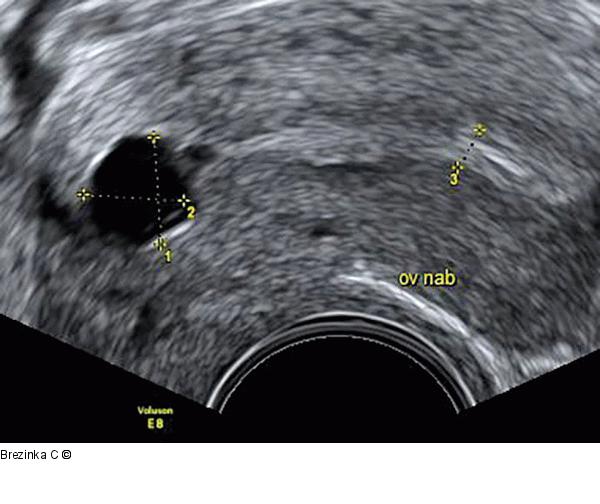

Abbildung 1: Ovulum Nabothii Ein 10 × 10 × 8 mm großes Ovulum Nabothii im Vaginalultraschall. Der echodensere, hellere Anteil der hinteren Muttermundslippe wird durch distale Schallverstärkung verursacht. |

Ein 10 × 10 × 8 mm großes Ovulum Nabothii im Vaginalultraschall. Der echodensere, hellere Anteil der hinteren Muttermundslippe wird durch distale Schallverstärkung verursacht. |